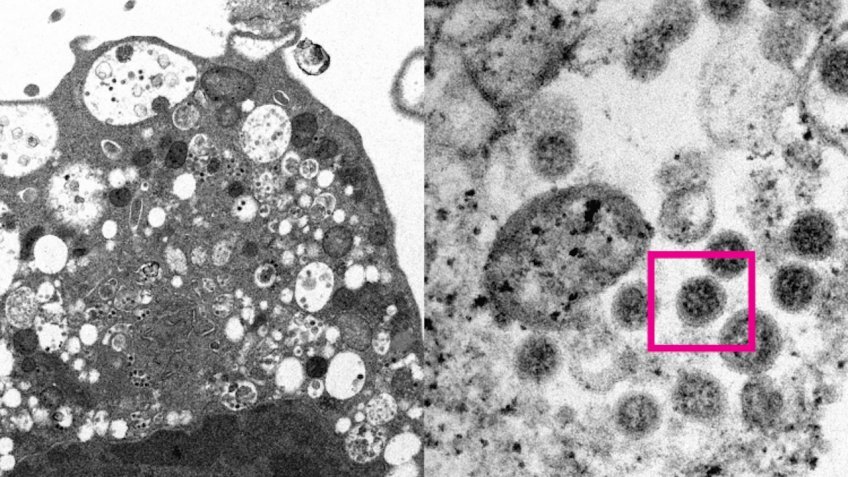

В России выявили первые два случая заражения омикрон-штаммом коронавируса. Завезли его приехавшие из ЮАР путешественники. Основные симптомы при заражении штаммом коронавируса "омикрон" — это выраженная слабость, температура, головная боль, кашель и снижение аппетита, об этом РИА Новости рассказала заместитель директора по клинической работе Московского НИИ эпидемиологии и микробиологии имени Габричевского Роспотребнадзора, доктор медицинских наук Татьяна Руженцова. По ее словам, указанные симптомы могут сопровождаться типичными для коронавирусной инфекции поражениями легких и других органов. Руженцова добавила, что в настоящий момент данных об особенностях проявлений, вызванных "омикроном", немного, однако со временем их должно стать больше.